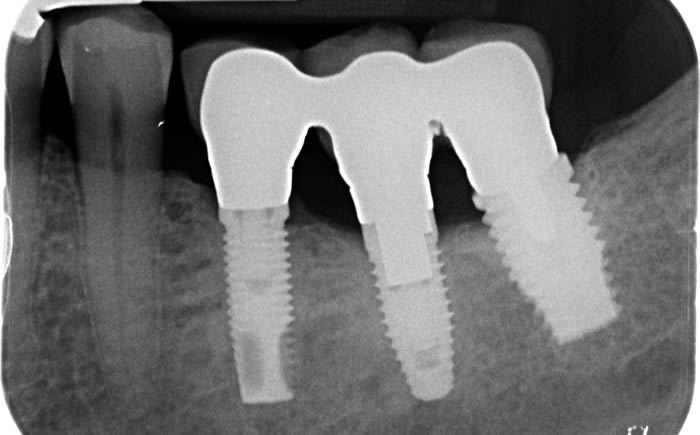

Back teeth replaced by dental implants

Case One (3 images)

Missing lower teeth replaced by three dental implants and crowns.

Case Two (5 images)

Six missing lower back teeth replaced by dental implants